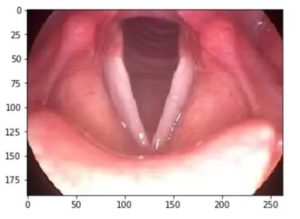

Связки в горле фото

На внутренней поверхности гортани с каждой стороны находятся по две складки: волокнистые — ложные ые связки и волокнисто-мышечные — истинные ые связки, разделенные между собой щелью V-образной формы, носящей название ой щели, которая отвечает за формирование звуков (более подробно о структурах гортани можно прочитать в следующих статьях: мышцы гортани, хрящи и суставы гортани, полость гортани, ые складки гортани и функции гортани).

Голосовые связки образуют ую щель. От ее ширины и от степени натяжения самих связок зависит, как изменяется голос. И то, и другое определяется сокращением той или иной поперечно-полосатой мышцы. Поэтому, рассмотрев хрящевой, суставной и связочный аппараты, логично обратить внимание и на мышцы гортани. Чтобы понять принцип, заложенный в основе движения гортани.

Звуки, которые издает человек, возникают из-за вибрации ых связок в момент когда воздух проходит из легких назад в ротовую полость; из звуков человек образовывает слова. При вдохе, как и при выдохе, когда человек не разговаривает, его ые связки расслаблены и прислонены к стенкам гортани так, чтобы воздух проходил без какого-либо сопротивления.